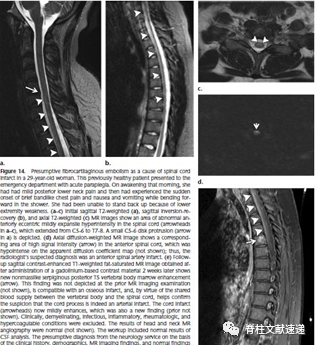

椎间盘组织脊髓纤维软骨栓塞

1961年,Naiman等人首次描述了这种类型的栓塞。相当多的“特发性”脊髓梗死可能是由于纤维软骨栓塞引起的。纤维软骨栓塞可以是动脉或静脉。在病理检查中,纤维软骨栓塞确实存在于节段静脉、小静脉、动脉和小动脉内,通常同时存在于椎体的静脉窦内。

血管和髓核之间需要存在某种类型的接触,才能使得椎间盘组织到达血管系统。

症状通常包括在相对较小的创伤或体力劳动后严重的背部或颈部疼痛。通常有一个无症状的时间间隔,之后会出现急性、快速发展为四肢瘫痪或截瘫,这是脊髓血管损伤的典型表现。

图注:如椎间盘组织逆行进入节段动脉(箭头),通过动脉直接流动或从窦进入动静脉。栓子随后通过顺行流到达脊髓,导致脊髓多层次梗死,通常位于脊髓前动脉分布区(脊髓腹侧阴影区)。栓塞物质也可以延伸到椎体的血液供应中,引起骨髓梗死(椎体背侧阴影区)。

图注:29岁女性,纤维软骨脊髓梗塞,因急性截瘫被送到医院。当天早上醒来时,她有轻微的后下颈部疼痛,淋浴时突然出现短暂的带状胸痛和恶心呕吐,下肢无力。